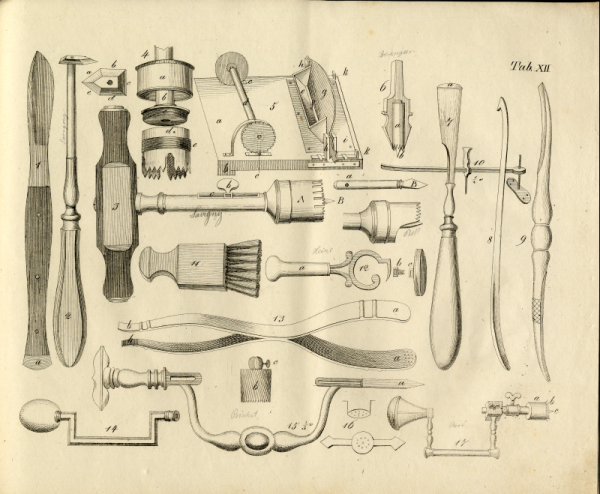

(14) 1829 Surgical Instruments via Bibliodyssey on Flickr

This Flickr set contains vintage surgical tool images galore!